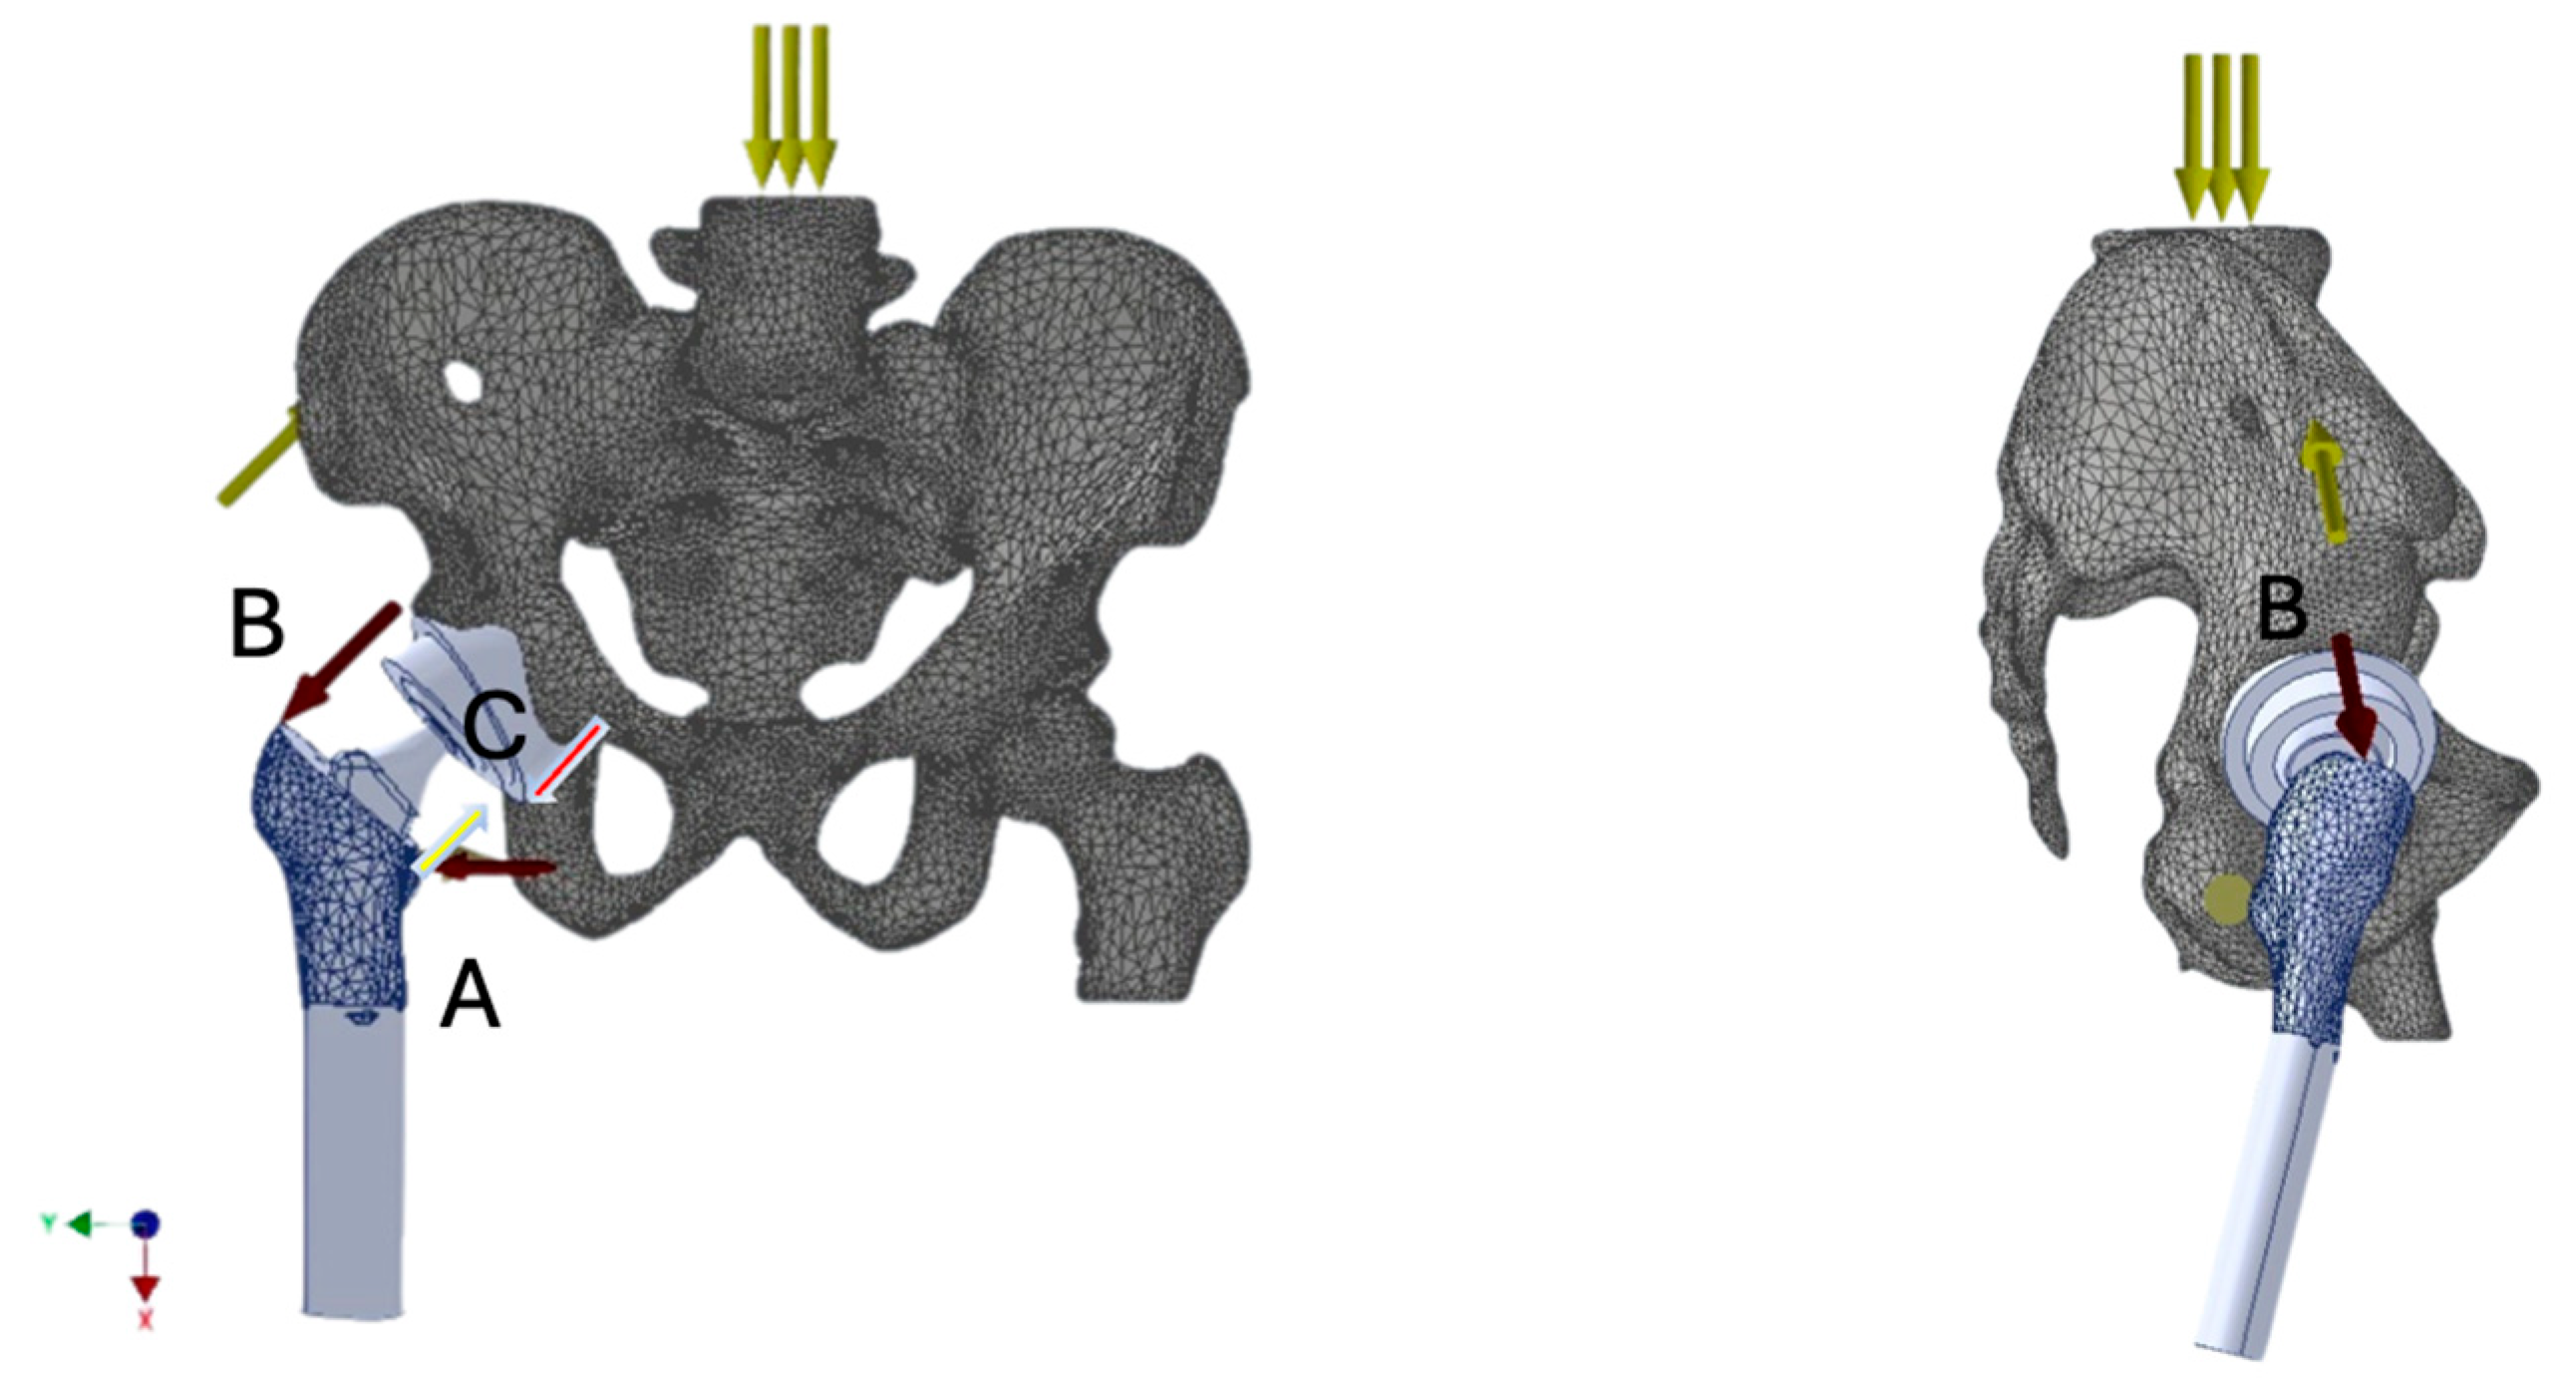

Figure 1. Muscle force vectors analyzed in the study acting on the prosthetic hip joint: adductor group (A), gluteal muscles (B), and iliopsoas muscle (C). Load distribution during single-leg stance is presented (↓↓↓).

Understanding the biomechanics of the prosthetic hip joint is crucial for establishing optimal implantation principles. Such knowledge enables analysis of the distribution of forces acting on the prosthesis during limb loading. The direction and magnitude of these forces can compromise joint stability and, under certain external conditions, predispose to dislocation. These forces result from both the mechanical load transmitted through the joint and the tension generated by the activity of specific muscle groups, primarily the quadriceps femoris, iliopsoas, gluteus minimus and medius and indirectly maximus as well, adductors, and rotators [Figure 1]. Repetitive sub-failure cycles can accumulate micro-damage and reshape local stress–strain fields, thereby elevating fatigue failure risk. Recent data-driven work demonstrates that spatial–temporal patterns extracted from these fields can predict ligament fatigue mechanisms and failure risk, complementing conventional finite-element analyses [4].

Muscle force models acting on bone structures (with prosthetic elements implanted) were developed as resultant force vectors representing the load on the hip joint during single-leg stance. The muscle groups and their roles included:

• Gluteal muscles—thigh abduction and primary stabilizers of the pelvis in the coronal plane;

• Iliopsoas—hip flexor;

• Adductor muscles—thigh adduction and internal rotation.

The muscle force vector values were adopted from literature sources [8], using an average force equivalent to 3–4 times body weight, expressed in Newtons (N).